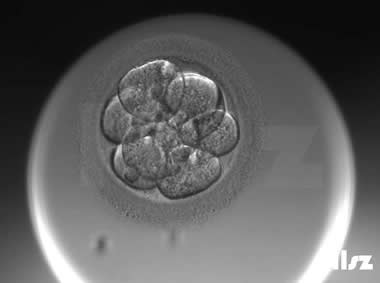

下面视频是胚胎在时差培养箱中培养至D3的整个过程,图片是D3(第68小时)的卵裂期胚胎图,本文D3胚胎评价是以D3时间点图片的形态学为依据,胚胎评级如下:

| Ⅱa级:该枚D3胚胎为6细胞,碎片不超过10%,因此评级为Ⅱa级。 | |